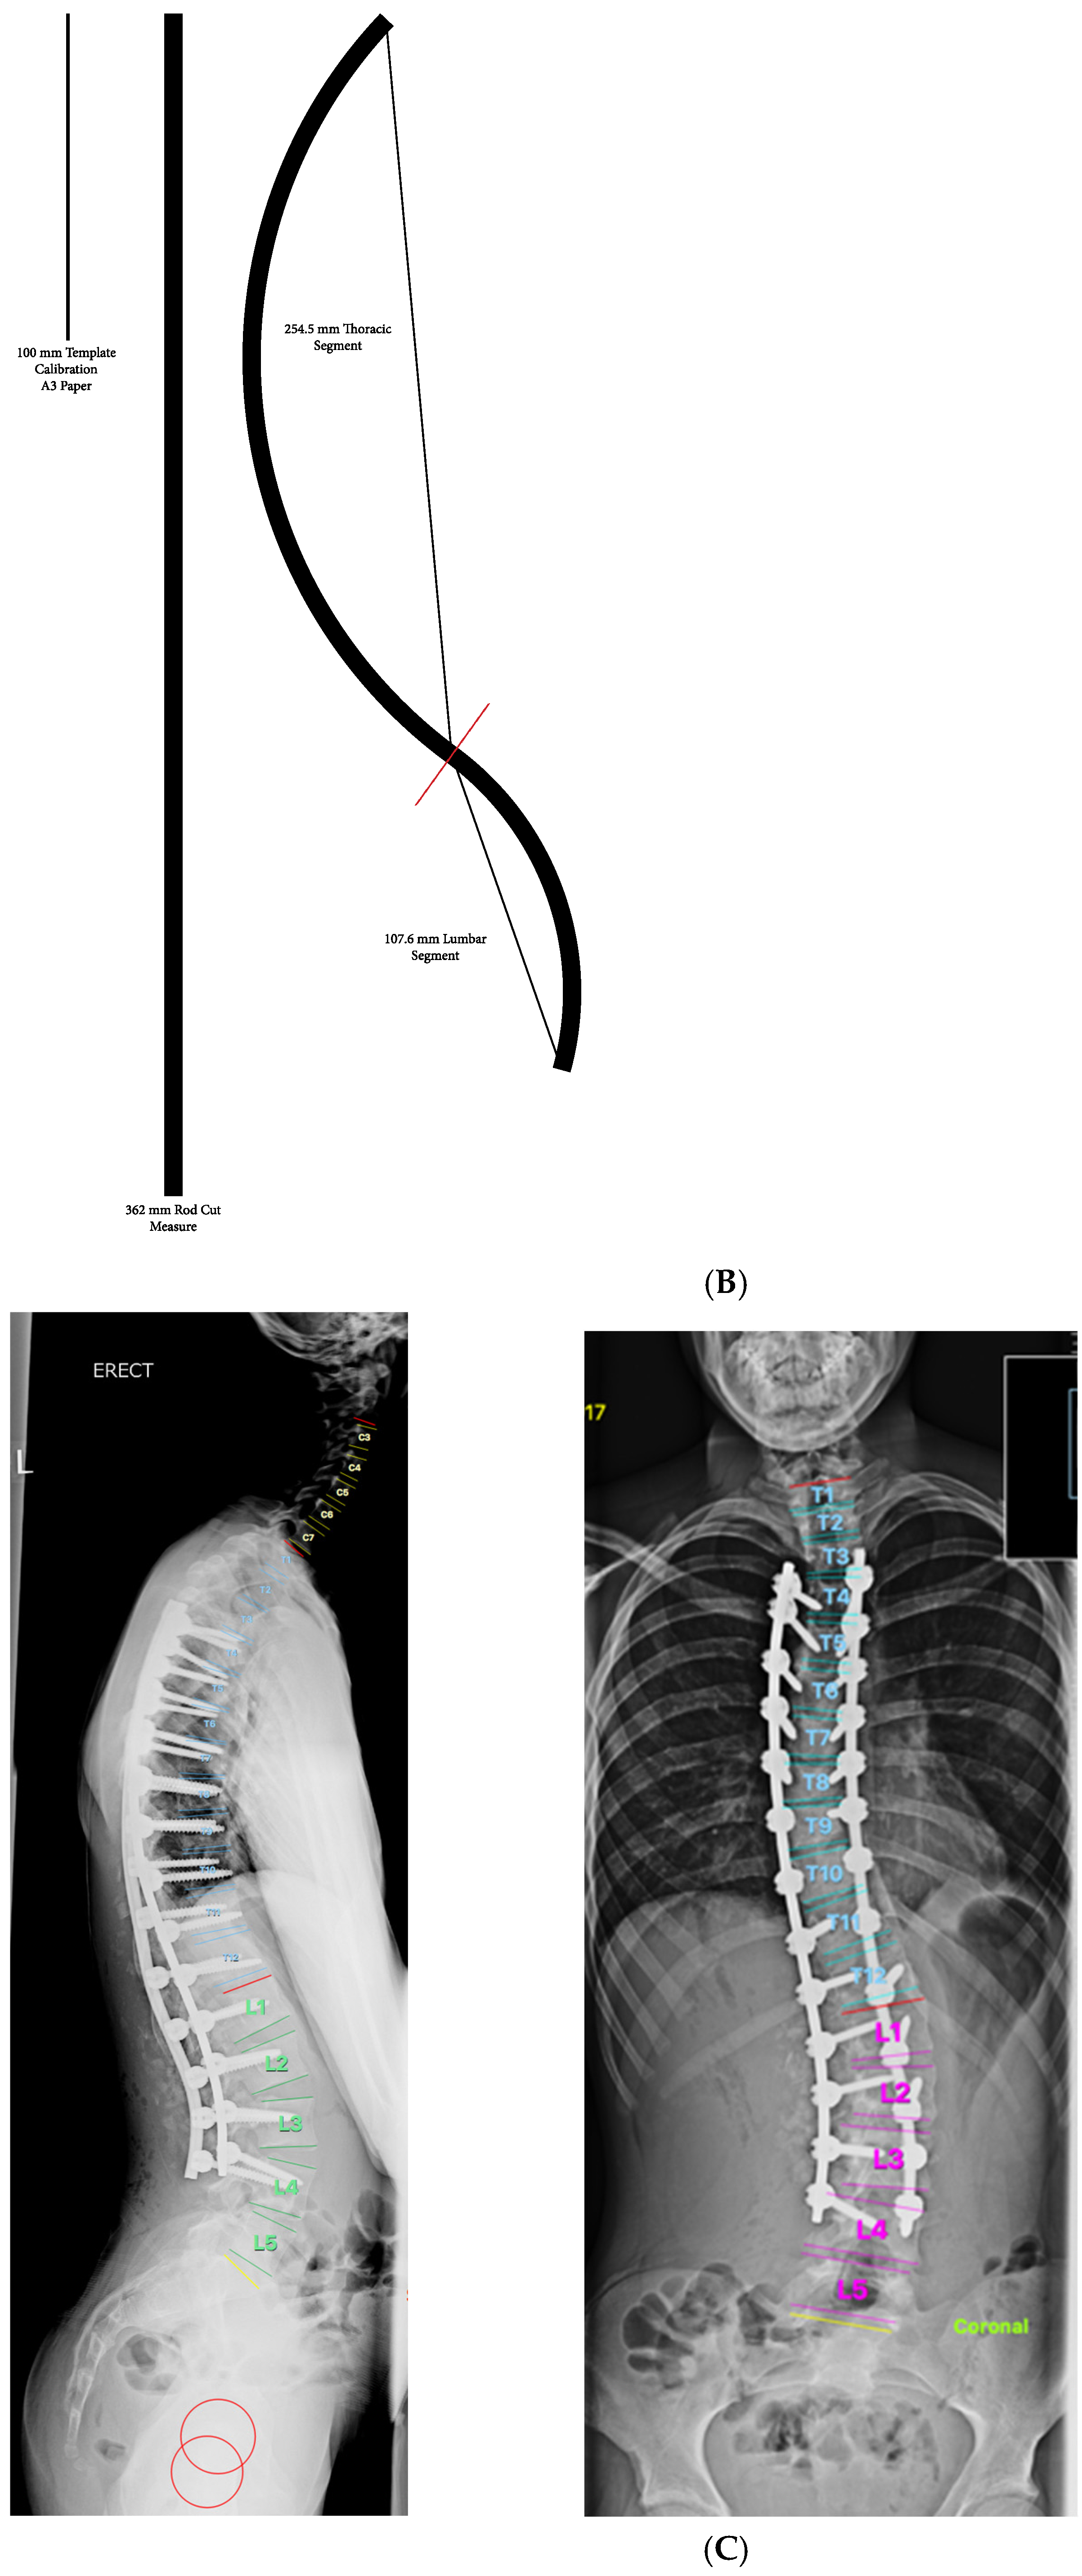

2. Materials and Methods